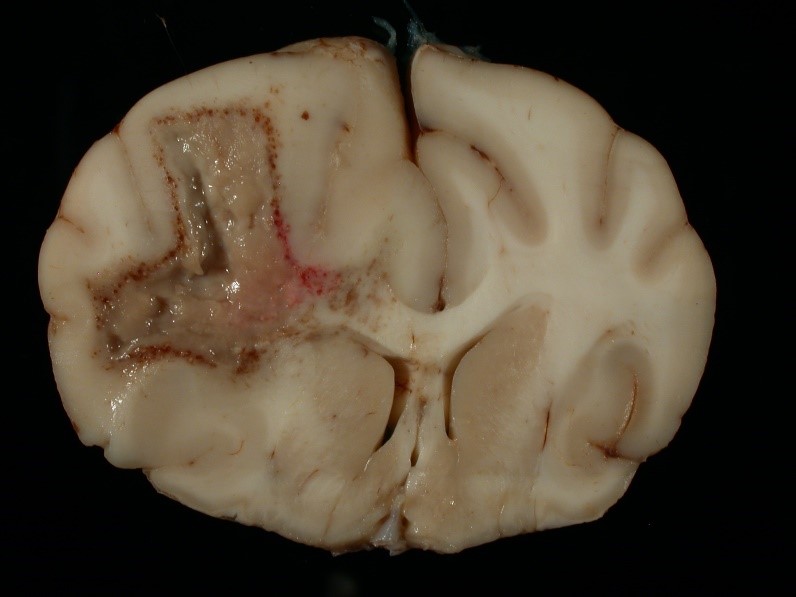

The image depicts a brain from a dog. In this type of necrosis, enzymatic digestion of cells predominates over protein denaturation and grossly (macroscopically), there is accumulation of soft, viscous, fluid. This is an example of what type of necrosis?

Liquefactive (lytic) necrosis